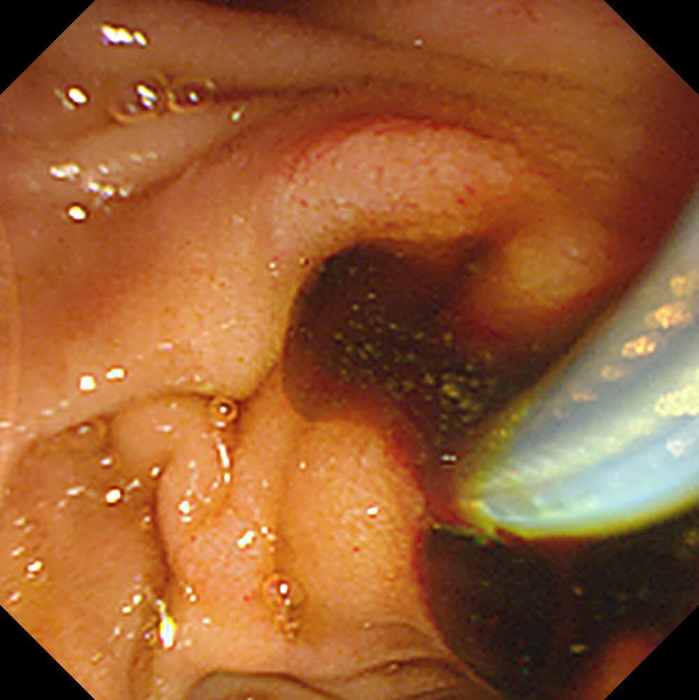

大量黑色胆汁流出

重症胰腺炎合并胆管结石病情凶险,若不及时干预,可能引发感染性休克等致命并发症!医务科组织的多学科会诊迅速启动,消化内科团队凭借精湛技术,通过ERCP(经内镜逆行胰胆管造影术)为患者实施鼻胆管置入术,精准引流胆汁、解除梗阻。